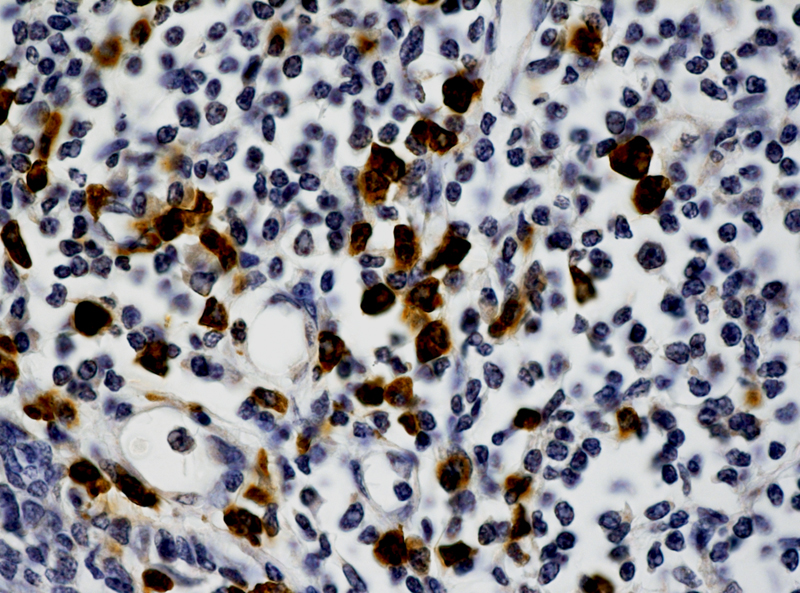

Human papillomaviruses (HPVs) induce a variety of proliferation lesions, leading to onset of squamous cell carcinoma (SCC) of the various tissues. HPV type 16 and 18 are responsible for about 70% of cervical cancer cases. We offers fluorescein labeled HPV probes for specific detection of HPV 16 and 18 genotype. The probes allow the localization of specific HPV viral DNA sequences in cultured cell lines,

cytopathology specimens, and FFPE tissue sections. It is the only method permitting detection of HPV viral DNA in a morphological context. Combined with the super sensitive ISH Detection systems, the probes offer reliable, highly sensitive and easy-to-perform assays.